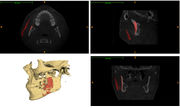

| 16:14, 10 June 2015 | ResultsFigure.jpg (file) | 247 KB | 1 | ||

| 16:10, 10 June 2015 | 3Dsurfacemodel.jpg (file) | 122 KB | Orthognathic registration result | 1 |